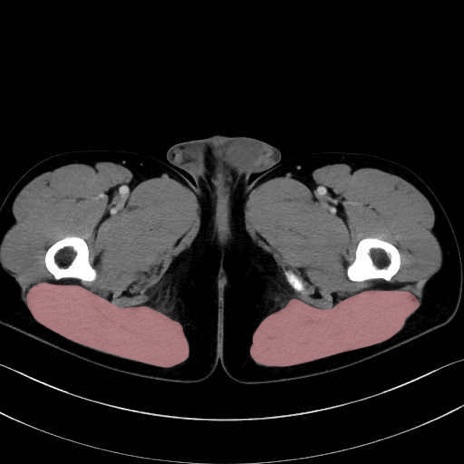

5. 大腿前面(大腿四頭筋群・伸筋群)

縫工筋 (Sartorius)

大腿直筋 (Rectus femoris)

外側広筋 (Vastus lateralis)

中間広筋 (Vastus intermedius)